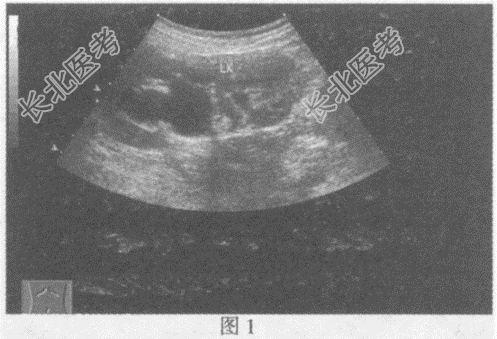

- 单项选择题临床资料:女, 9岁,自述左侧腰部疼痛2年余。

超声综合描述: 左肾增大,上极部集合系统内可见4.3cm×3.1cm无回声(图1), 形态不规则;下极部集合系统未见分离。左输尿管全程显示(图2、图3), 内径1.7~2.7cm,左输尿管末端可见一类圆形无回声区突向膀胱内(图4), 囊壁薄而清晰、规则,动态观察无回声区大小随左输尿管蠕动有节律变化。